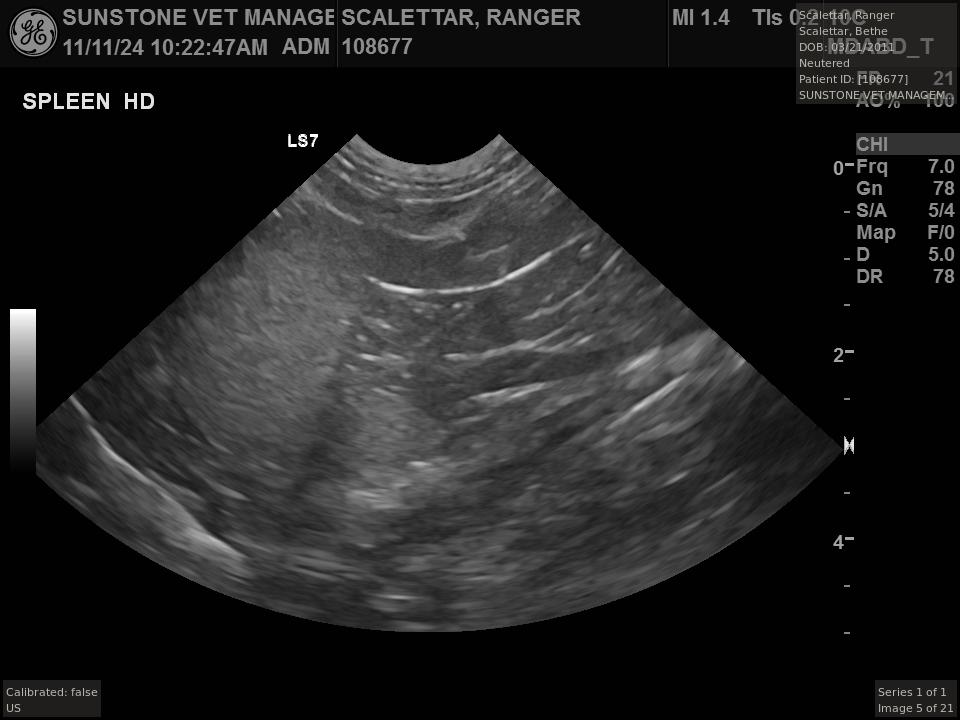

The veterinarian generated a series of images showing different organs and substructures by

changing the position and orientation of the ultrasound transducer. The images were collected

in a defined order, which is repeated from patient to patient, ensuring that nothing is missed. In

Ranger's case, the sonographer collected about twenty images during an examination that

lasted about fifteen minutes.

The sonographer stated that Ranger's ultrasound images were largely normal for an older cat. In particular, they show changes in the kidneys that are commonly noted in geriatric cats and that reflect a risk for the development of chronic kidney disease. However, the images did not show any significant abnormalities in Ranger's stomach, intestines, and associated lymph nodes. Nonetheless, the results did not rule out recurrence of Ranger's small cell lymphoma.